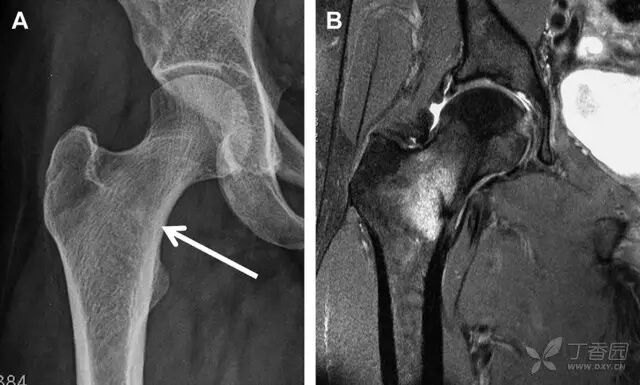

股骨头骨折常与髋关节脱位有关。需要注意的是那些既不是因剪力损伤也不是因直接暴力作用造成的骨折。这些类型的骨折可能十分轻微。提倡应用 CT 检查,不仅可诊断骨折,而且能评估关节内骨折碎片的位置(图 6)。

图 6 股骨颈骨折伴髋关节脱位。A 股骨头上外侧轮廓缺失(空箭头)注意嵌入上方关节间隙的骨折碎片(黑色箭头)B 冠状位 CT 多维重建(MPR)证实骨软骨碎片(白色箭头)和关节上方的另一个碎片(空箭头)